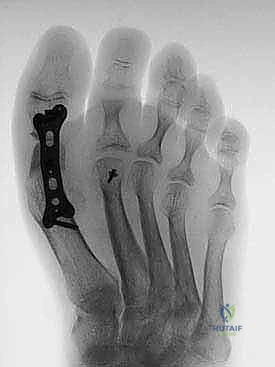

6. التثبيت الداخلي الصلب (Rigid Internal Fixation)

لضمان التئام العظام (وهو ما يستغرق عدة أسابيع)، يجب تثبيت المفصل والطعم العظمي بقوة شديدة. يستخدم الأستاذ الدكتور محمد هطيف أحدث الشرائح المعدنية المصممة خصيصاً لاندماج إبهام القدم (Anatomical Locking Plates) والمسامير التيتانيوم. يتم وضع الشريحة فوق المفصل وتثبيتها بمسامير تمر عبر الطعم العظمي لضمان ثباته المطلق.

7. الإغلاق والتحقق بالأشعة

يتم أخذ صور أشعة سينية داخل غرفة العمليات (Fluoroscopy) للتأكد من المحاذاة المثالية للإصبع، وتصحيح زاوية الارتفاع، والموضع الدقيق للمسامير. بعد ذلك، يتم إغلاق الجرح بخيوط تجميلية ووضع ضمادات معقمة وجبيرة واقية.

- الأشعة: يتم إجراء أول صورة أشعة سينية للمتابعة للتأكد من ثبات المسامير وبدء عملية الالتئام.

- إذا أظهرت الأشعة السينية علامات قوية لاندماج الطعم العظمي، يسمح د. هطيف بالتحميل التدريجي لوزن الجسم بالكامل أثناء ارتداء الحذاء الطبي الصلب.